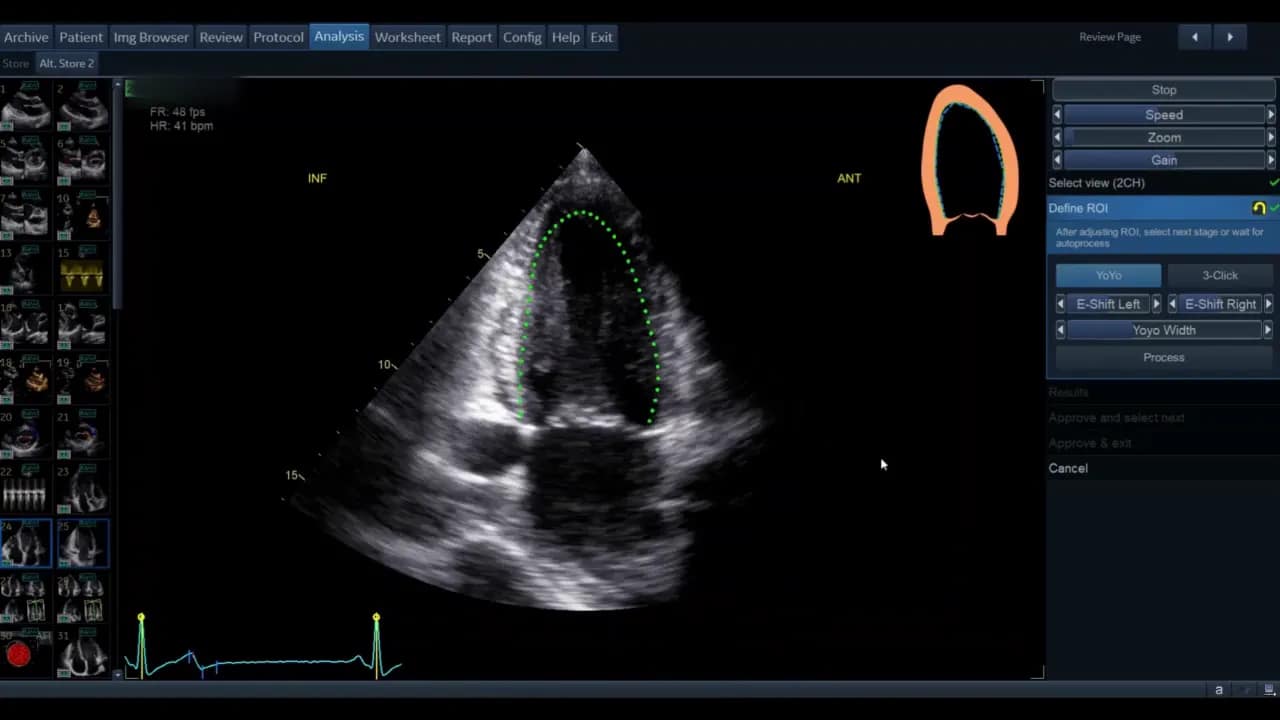

Sobald die Ansicht gewählt ist, gelangen Sie in die Phase der ROI‑Definition. Hier legt die Software die initiale Kontur für die automatische Wandsegmentverfolgung fest.

Die Standardkontur wird als grüne Linie (modellabhängig) angezeigt. Bewegen Sie den Cursor über diese Linie; rote Kreise erscheinen als Griffpunkte, die Sie anklicken, verschieben und loslassen können. Ziel ist eine möglichst genaue Platzierung entlang des inneren Myokardrandes ohne Papillarmuskeln und Trabekel zu ignorieren, soweit die Software dies zulässt.

- Wenn die vorgegebene Kontur passend ist, genügt das geringe Feintuning.

- Wenn die Kontur unbrauchbar erscheint, nutzen Sie die Drei‑Punkt‑Option. Dabei markieren Sie basal‑septal, basal‑lateral und den Apex manuell. Die Software interpoliert zwischen den Punkten.

Nach der manuellen Markierung können Sie die so erzeugte grüne Kontur wiederum per Griffpunkte feinjustieren. Ziel ist, dass die Kontur den endokardialen Rand im gesamten Zyklus plausibel abdeckt.